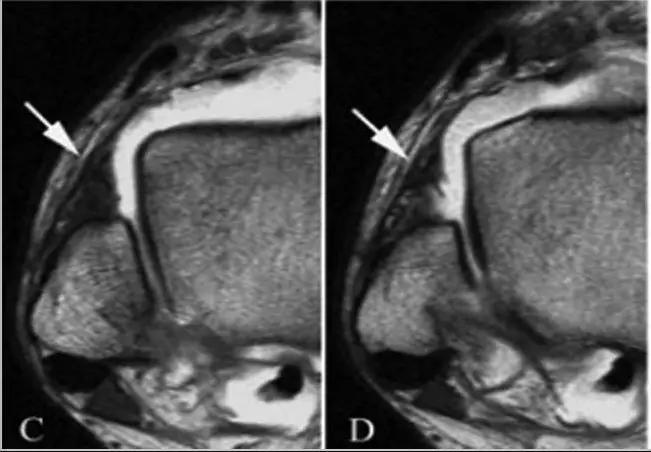

5.后内侧撞击综合症:

影像学表现为距骨胫骨间肌腱及趾长屈肌腱水肿、增厚,内踝及距骨后内侧骨赘形成。

轴位示意图示后内侧撞击综合征:M:内踝;L:外踝;TP:胫后肌腱;FDL:趾长屈肌腱;Talus:距骨。短箭:距骨胫骨间肌腱深层纤维;箭头:距骨胫骨间肌腱后部纤维。

X线平片示胫骨后部骨赘形成,MR质子像黑箭示胫骨内后侧骨赘形成,白箭示内后侧软组织增厚, 白箭头:胫后肌腱;黑箭头:趾长屈肌腱